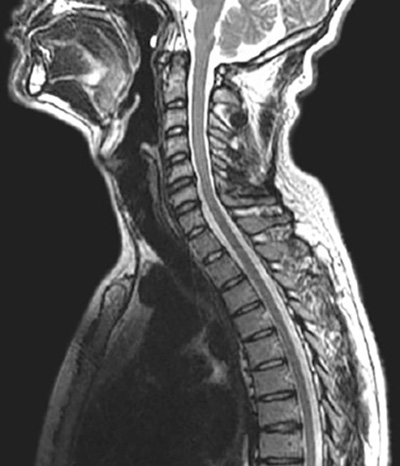

La resonancia magnética es una técnica muy utilizada para diagnosticar hernias discales en cualquier nivel de la columna, así como otras patologías medulares.

Ejemplos